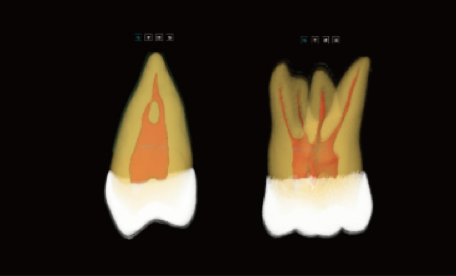

Análise Dentária 3D Abrangente: segmentação completa do dente com medições automáticas, planeamento do percurso de acesso e avaliação precisa de cáries.

Visualização Endodôntica Avançada: observação 3D de cáries interproximais, defeitos estruturais e morfologia dos canais radiculares, garantindo que nenhum canal passa despercebido.

Segmentação Completa da Estrutura Dentária: realce automático do esmalte, dentina, polpa e estruturas periodontais, permitindo a visualização das alterações morfológicas.

Mapeamento Avançado dos Canais Radiculares: visualização clara dos canais MB2 e em forma de C, apoiando um tratamento endodôntico preciso e minimizando o risco de canais não detetados.

Visualização Especial dos Canais Radiculares

vermite a visualização de morfologias especiais dos canais radiculares (MB2 e canais em forma de C), orientando os procedimentos endodônticos.

Ajuda a evitar a omissão de canais.